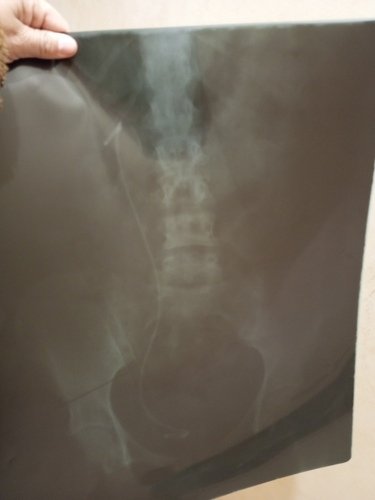

Me chamo Adriana,tenho 43 anos ,fiz um tratamento de câncer de mama em 2020,no qual eu ainda faço acompanhamento,em decorrência do tratamento do câncer ,tive sequelas no coração,fiquei com cardiopatia hipertensiva,entre outros problemas no coração,que estarei anexando o depois ,e hoje mesmo com todos esses problemas eu estou lutando com um problema renal,por conta de uma pedra que não sai,hoje eu me encontro com um cateter dupla J desde abril quando coloquei,agora dia 14 de setembro estarei fazendo uma cirurgia novamente,para a retirada do cateter e caso as pedras permanecem terei q colocar novamente,pq ele faz com que meu rim não pare,porém ela causa muita infecção urinária,por conta de ser um corpo estranho no meu,por isso estou em uma grande luta ,agora preciso retorna no cardiologista,até mesmo porque tenho alguns exames q precisam ser liberados pelo cardiologista pra mim fazer , até a cirurgia,mas não sei se vou conseguir até o dia da cirurgia,porém terei q passa após a cirurgia pra saber como ficou e tbm pra ser liberado alguns exames q só posso fazer com a carta dele ,por conta de ter risco de hemorragia, então venho por meio desta vaquinha ,pedir por favor quem puder me ajude,esse valor será pra pagar o cardiologista e os exames que se referem ao coração,como eco que tem ser feito na Jaú cordis ,por conta de eu não ter a mama de um lado,o aparelho tem q ser bem visível,e outros exames ,por conta de todas essas enfermidade só meu esposo trabalha,pagamos aluguel,e estive afastada até outubro do ano passado,mas agora estou na luta com o INSS pra me afastar,mas tá complicado,agora vou ver se com a carta do cardiologista e os exames eu consigo entra com o pedido novamente, peço de coração quem puder me ajuda,que possa abençoar grandemente a vida de cada um 🙏🙏Vou deixa o meu pix tbm caso queira ,mas assim q der o valor necessário avisarei ,somente preciso mesmo com urgência por conta de ter q passa no cardiologista,desde agradeço,qualquer dúvida pode fala comigo 14981010376